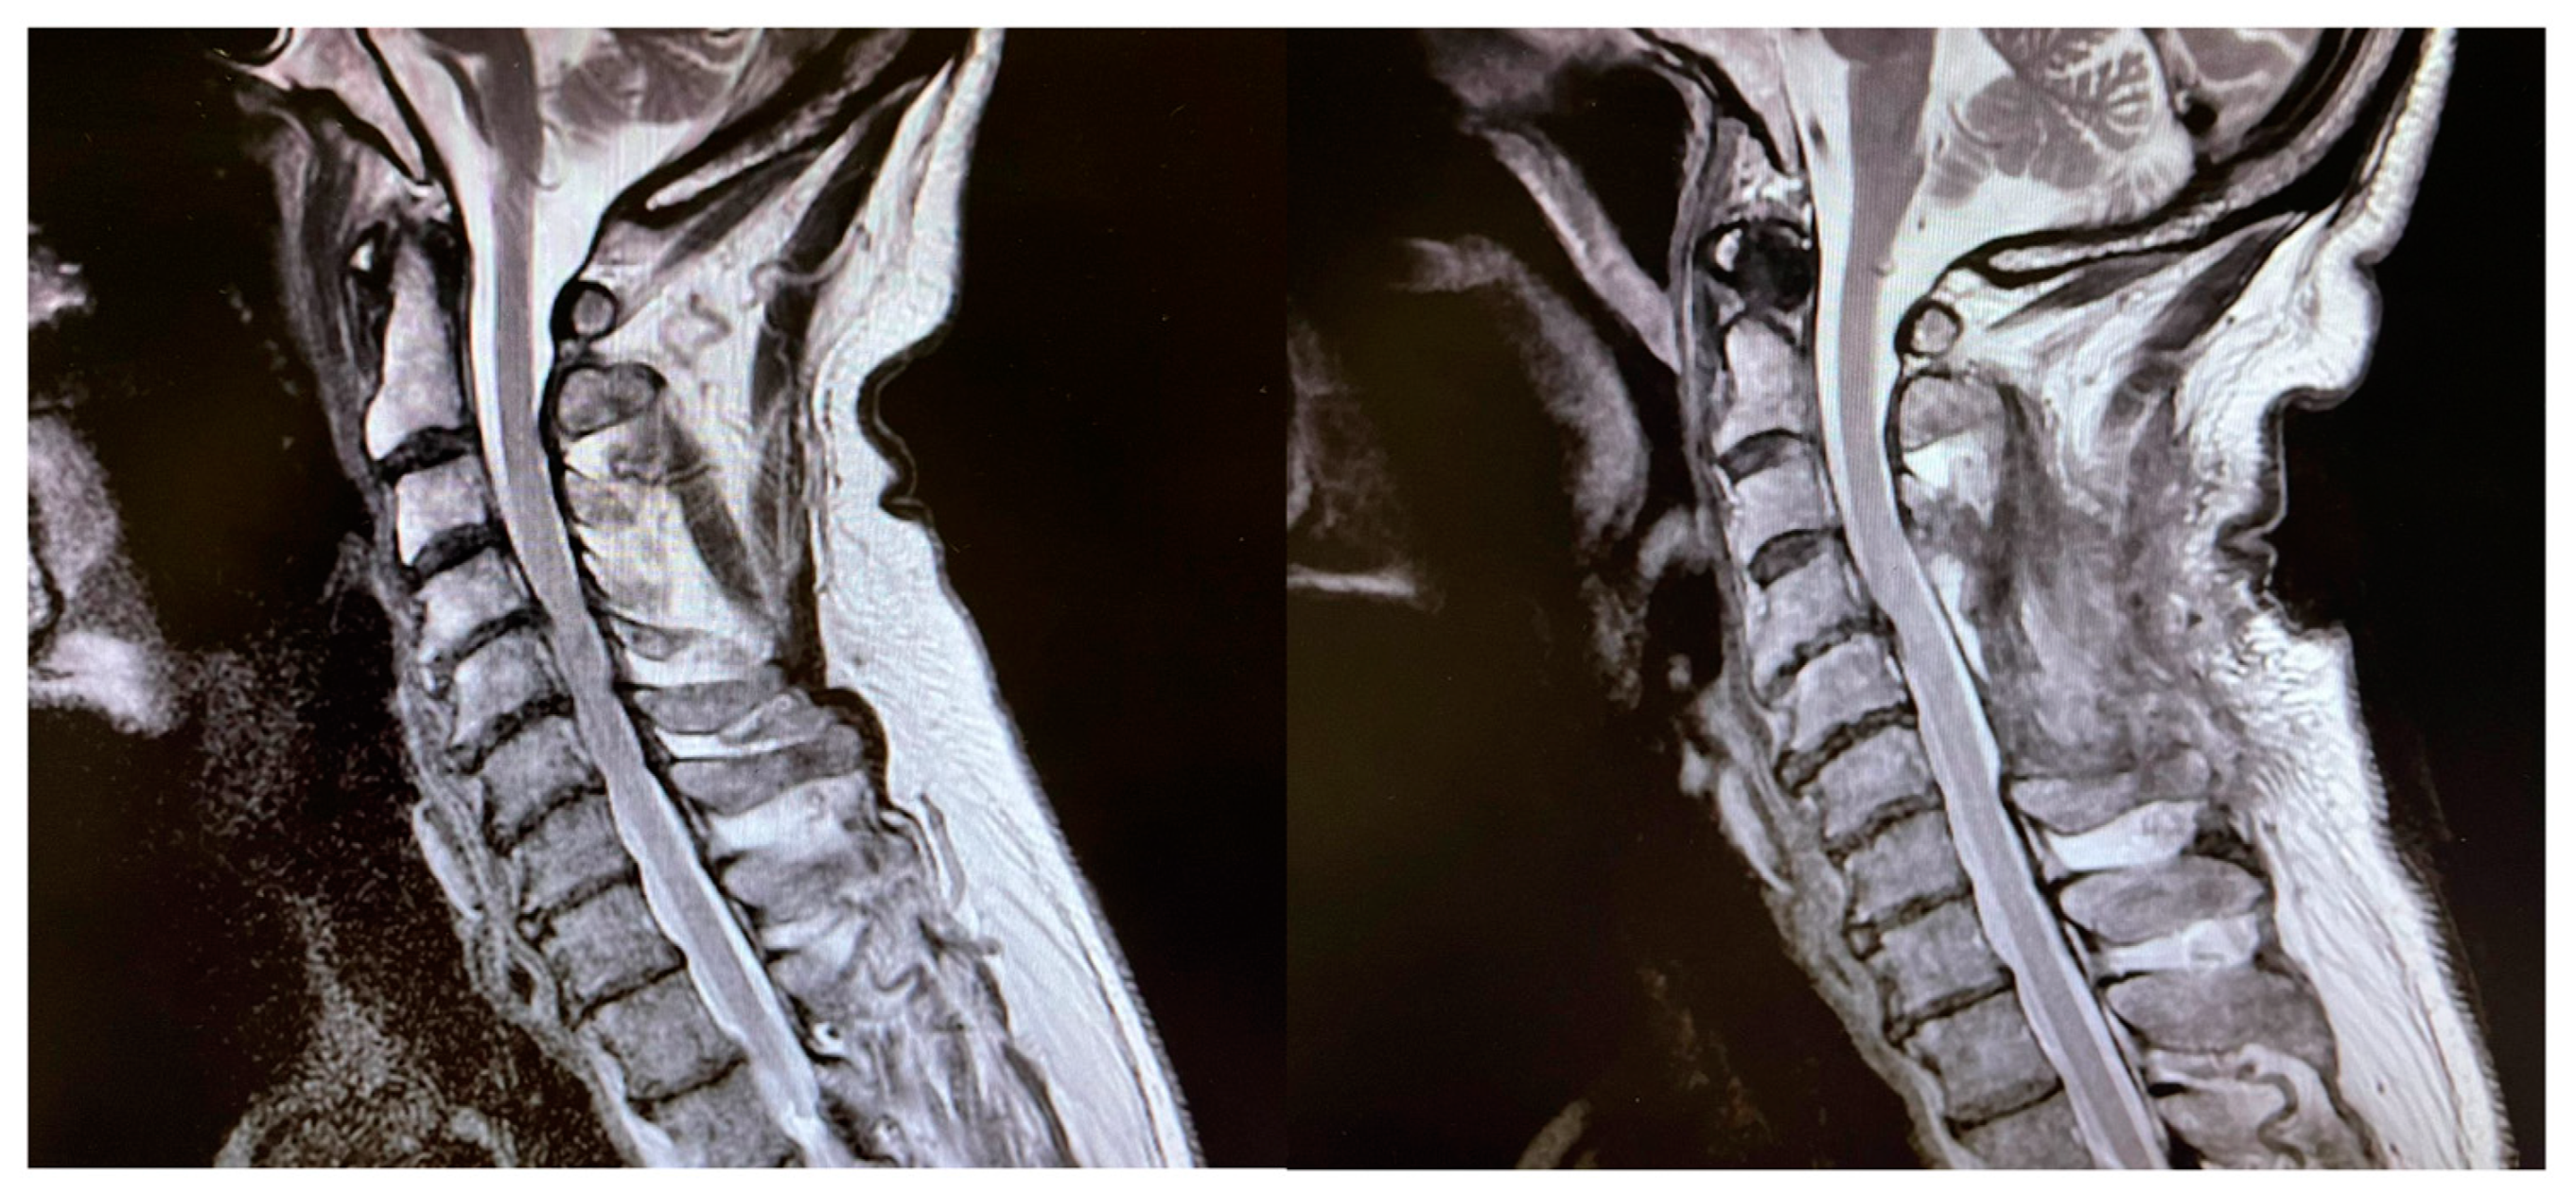

3.1. Patient Population

| Degenerative | 94% |

| Neoplastic | 6% |

| Surgical approach | |

| Posterior | 66% |

| Anterior | 33% |